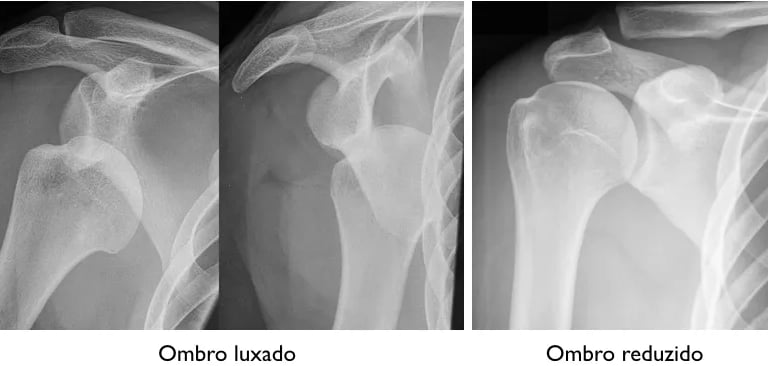

Luxação do Ombro

Luxação do ombro é a perda de contato entre a cabeça do úmero que perde o contato e a glenoide, a parte articular da escápula. O deslocamento causa geralmente as lesões de Bankart e Hill-Sachs. A lesão de Bankart é o destacamento dos do lábio, ou labrum, da glenoide. A função do lábio glenoidal é servir de ancoragem para os ligamentos e aumentar a estabilidade da articulação. Ela ocorre porque a cabeça do úmero tem um osso mais frágil do que o osso da glenoide.